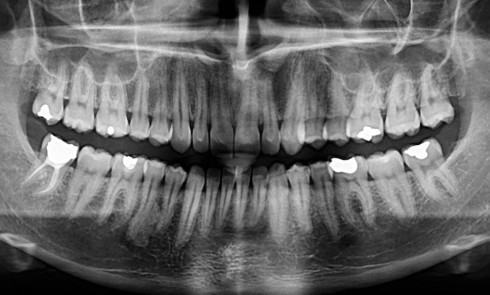

Troubles des conduites alimentaires : incidences sur la prise en charge orthodontique

Les troubles des conduites alimentaires sont définis clairement dans le DSM V (diagnostic and Statistical Manual of Mental disorders) [1]. On les définit comme des perturbations caractérisées par une obsession de la nourriture, du poids et de l’apparence qui affecte négativement la santé de l’individu. Cette définition et son origine indiquent clairement que nous sommes dans le domaine de la psychiatrie, ce qui occasionne parfois un frein dans la prise en charge odontologique ou orthodontique de ces patients. L’objectif de cet article est de démystifier, mais également de préciser les spécificités de ces prises en charge et de repositionner l’orthodontiste dans son rôle de personnel médical clé, au-delà de son geste technique.

• L’anorexie nerveuse, la plus connue, se caractérise par une volonté pathologique de minceur. Ces patients présentent un IMC (indice de masse corporelle) inférieur à 17,5 (HAS). Il en existe deux formes : l’anorexie restrictive et l’anorexie purgative.

• Dans l’anorexie purgative, l’alimentation est suivie d’épisodes de vomissements et/ou la prise de diurétiques, laxatifs, médicaments coupe-faim, voire une activité physique excessive afin de rester « mince ».

• La boulimie consiste à absorber de grandes quantités d’aliments durant des crises régulières, quotidiennes ou plusieurs fois par semaine, suivies de phases de vomissements pour garder le contrôle du poids. Ces patients peuvent présenter un poids normal ou un IMC inférieur à 17,5.

• Le mérycisme consiste en une régurgitation répétée du bol alimentaire après un repas, ce qui est souvent difficile à évoquer avec un patient.

Ces troubles ont en commun une maladie psychiatrique qui se traduit par une souffrance psychique, une estime de soi dégradée, un isolement social plus ou moins marqué, des manifestations somatiques telles que troubles gastriques, carences alimentaires, hypokaliémie en cas de vomissements répétés, ostéoporose, perturbations hormonales… Il est important…